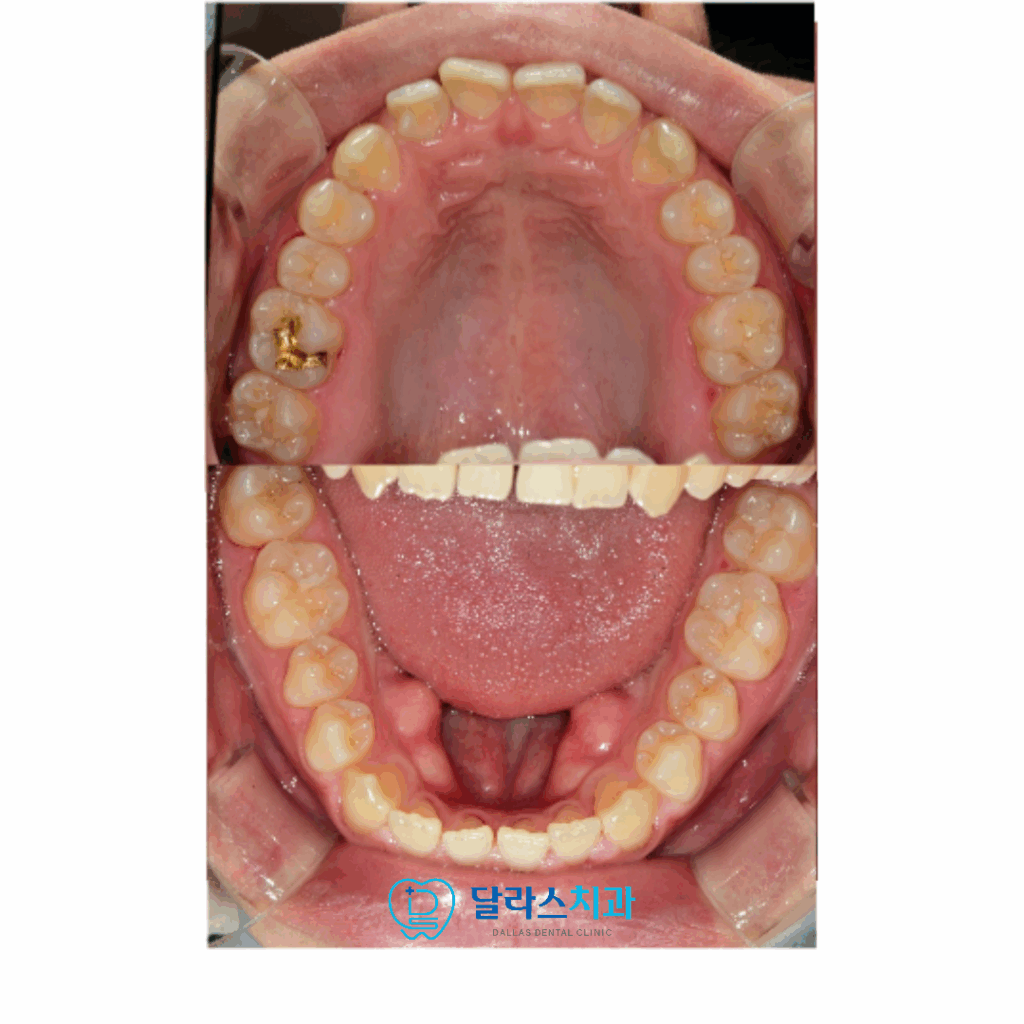

위아래의 치아를 보면 전치부가 약간씩 틀어져 있는 것을 확인 할 수 있습니다

오른쪽 위의 두 번째 앞니를 보면 치아의 모양이 기형적인 것을 확인할 수 있습니다.

이 기형치로 인해서 교합관계가 방해를 받아서 정상적으로 물리지 않고 있었습니다.

또 한 가지의 문제점은 송곳니가 너무 깊게 맞닿아있는 딥바이트로 인해서

정상적인 “Canine guidance” 가 이루어지지 못하고 있었습니다.